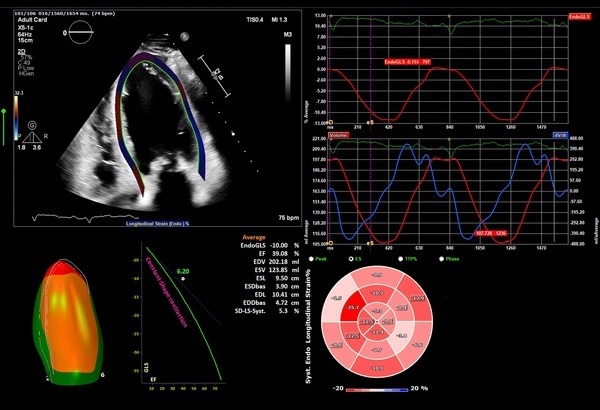

AutoStrain LV

Auto View Recognition、Auto Contour Placement、スペックル・トラッキングなどの高度な自動化テクノロジーが採用されており、ボタンを1回押すだけで、短時間で再現性の高いGlobal Longitudinal Strain(GLS)が得られます。